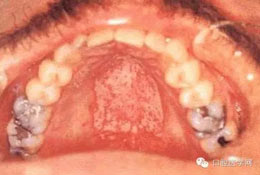

(一)念珠菌病

2.增生型: 為堅固而致密的白色斑塊或針頭大小的小結節(jié),附著于紅色病變區(qū)。

3.偽膜型: 為白色或黃色可除去的斑點或斑塊。